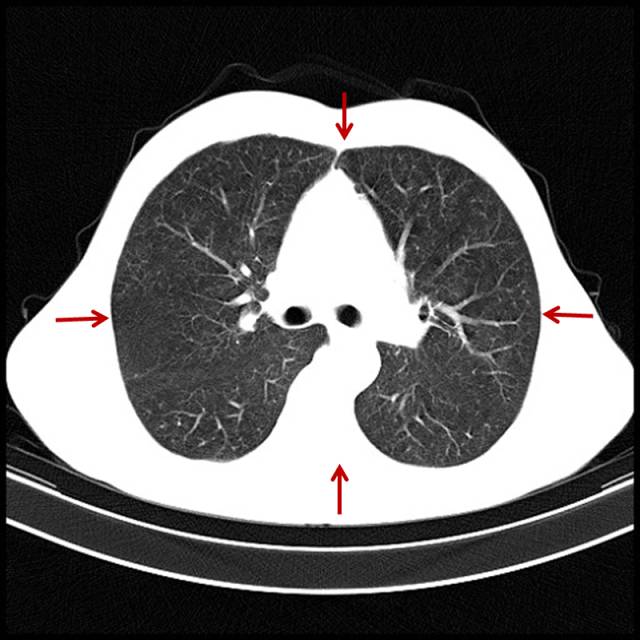

■ 吸烟导致肺气肿

肺气肿是指终末细支气管远端的气道弹性减退、过度膨胀、充气和肺容积增大或同时伴有气道壁破坏的病理状态。看看CT表现。